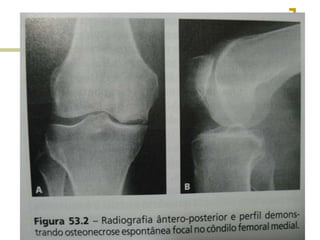

Rx

Diagnóstico  Os achadosclínicos precedem os achados radiográficos cerca de 1 a 8 meses  Rx – pobre  TC – SPECT  RNM – quantificar a lesão  Cintilografia – diagnóstico precoce, 8 semanas – área quente

 Unilateral – porção lateral do côndilo medial